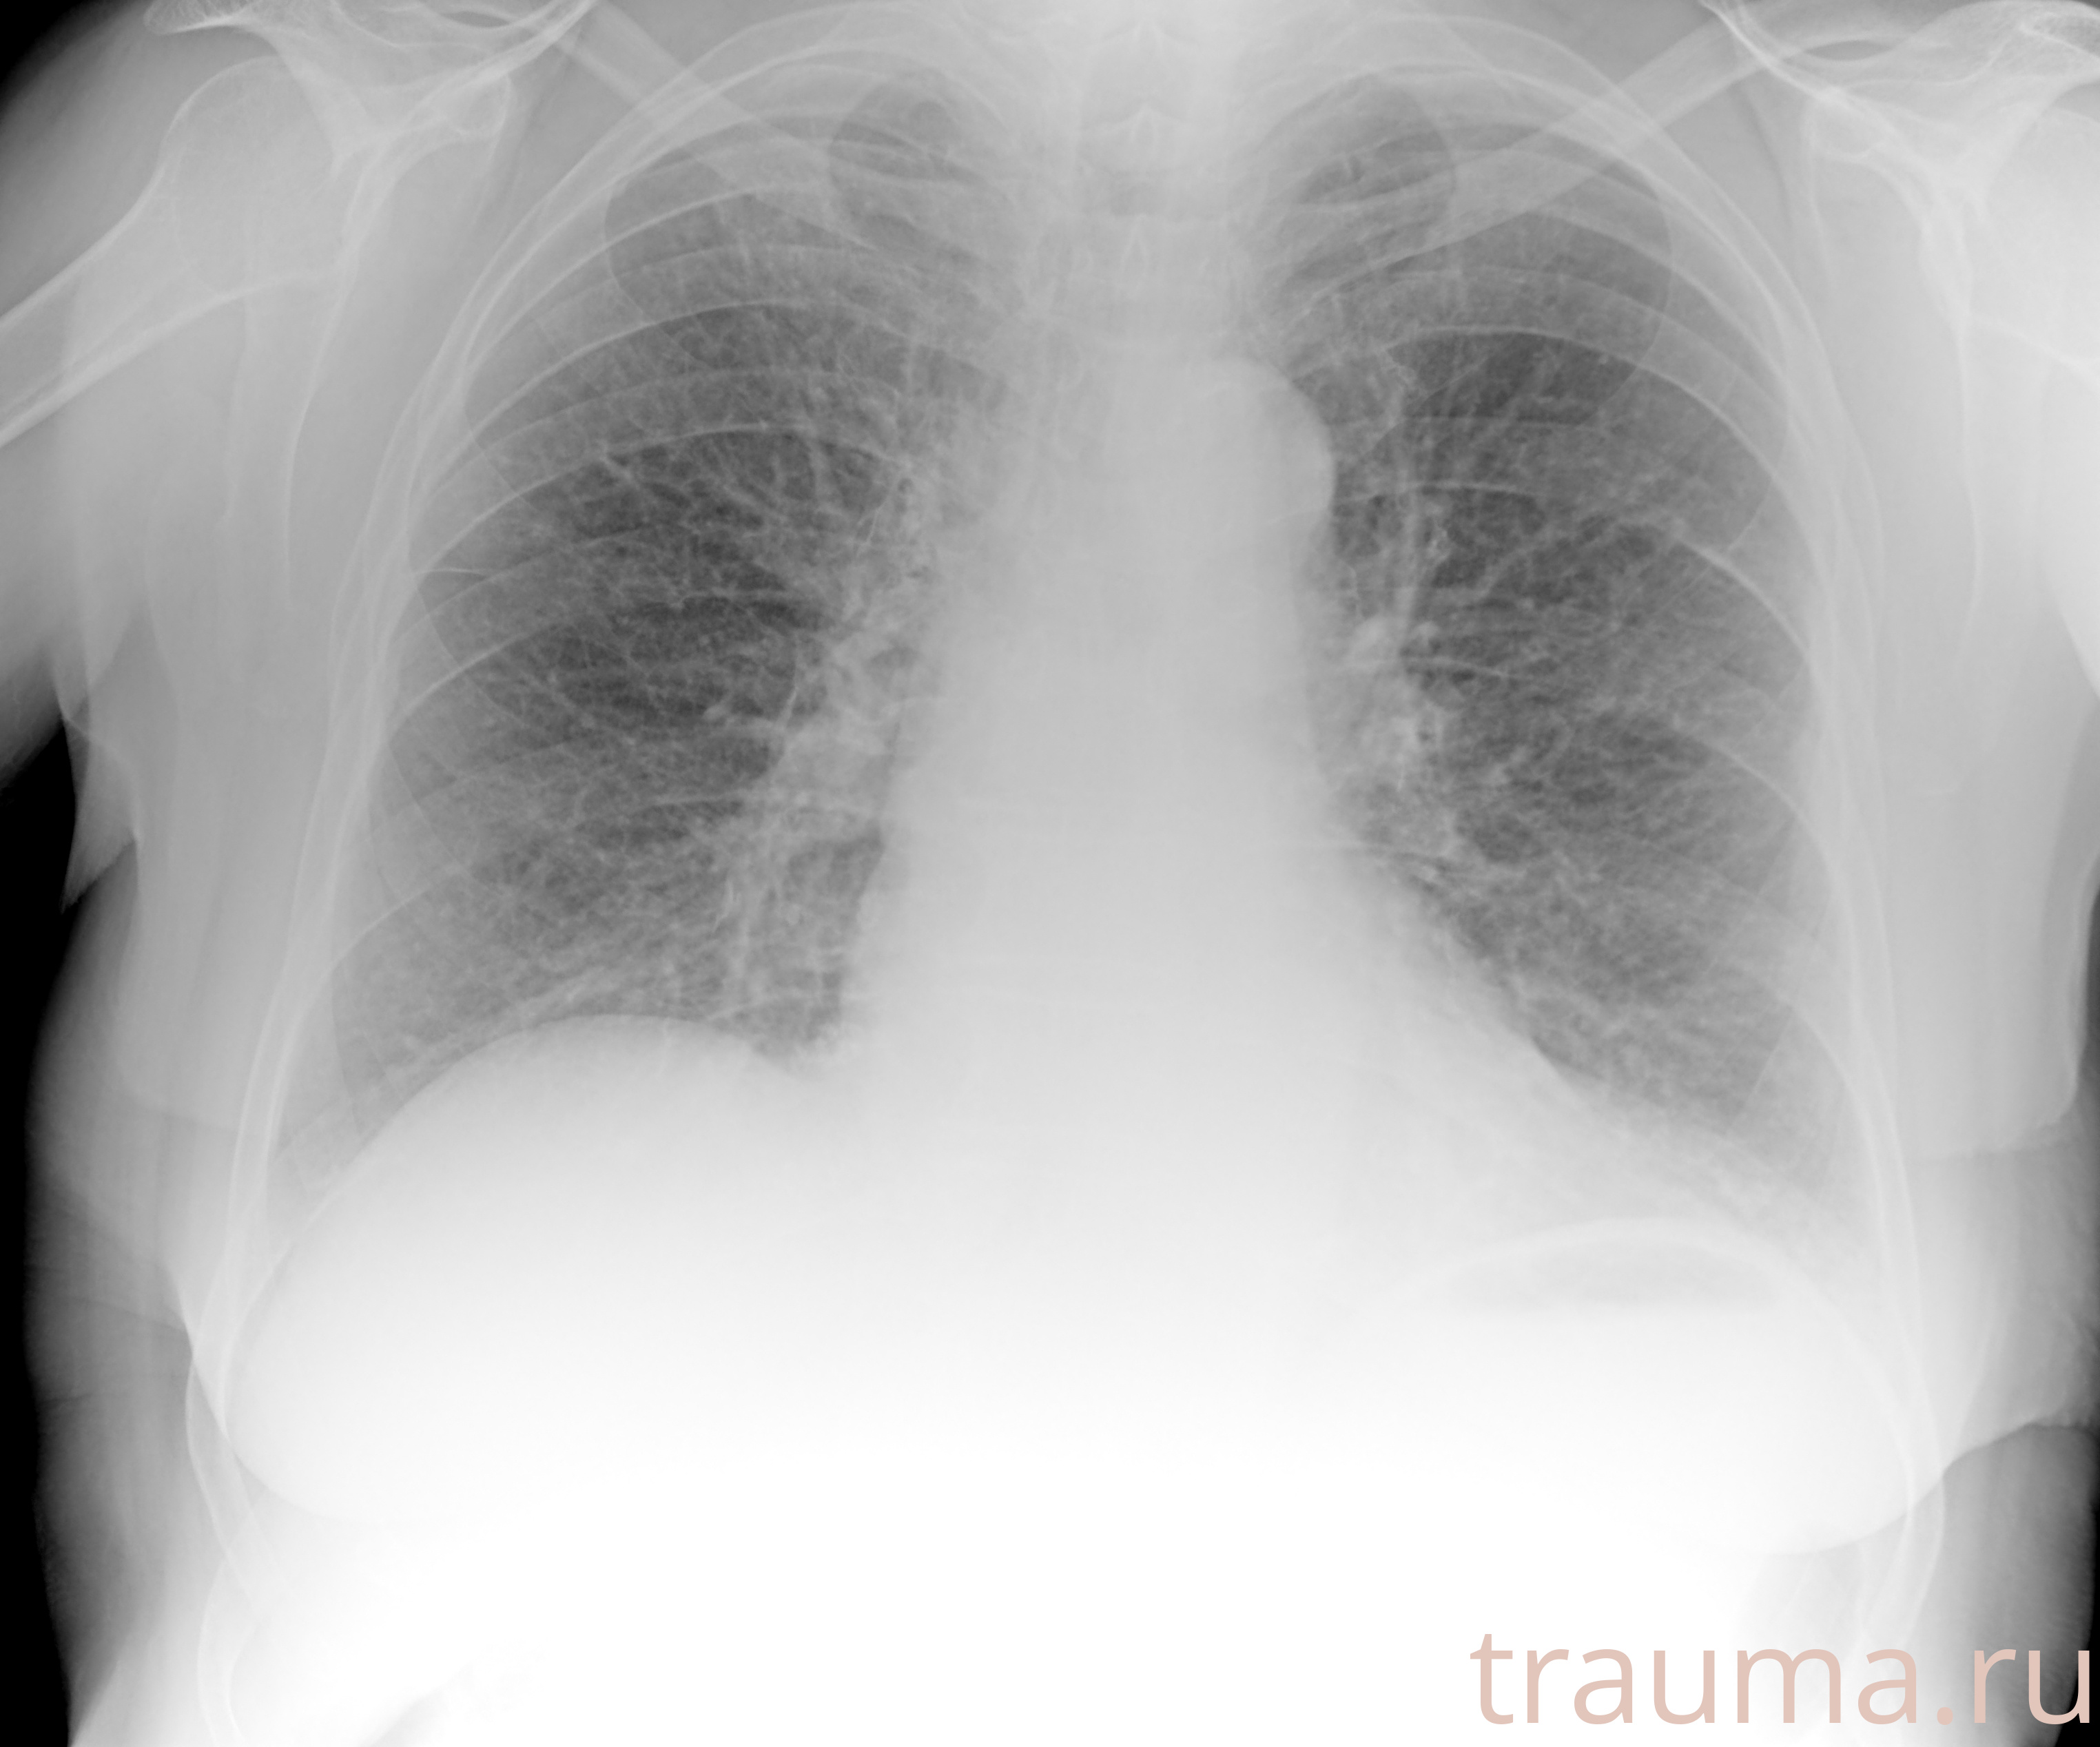

Рентгенограммы

Рентген на дому: по вашему адресу приезжает врач-рентгенолог, травматолог-ортопед с мобильным рентгеновским аппаратом, проводит диагностику травмы или заболевания, делает необходимые рентгенограммы, дает рекомендации по дальнейшему лечению. Получить качественные снимки в домашних условиях возможно благодаря уникальной методике, разработанной МосРентген Центром для института  Склифосовского